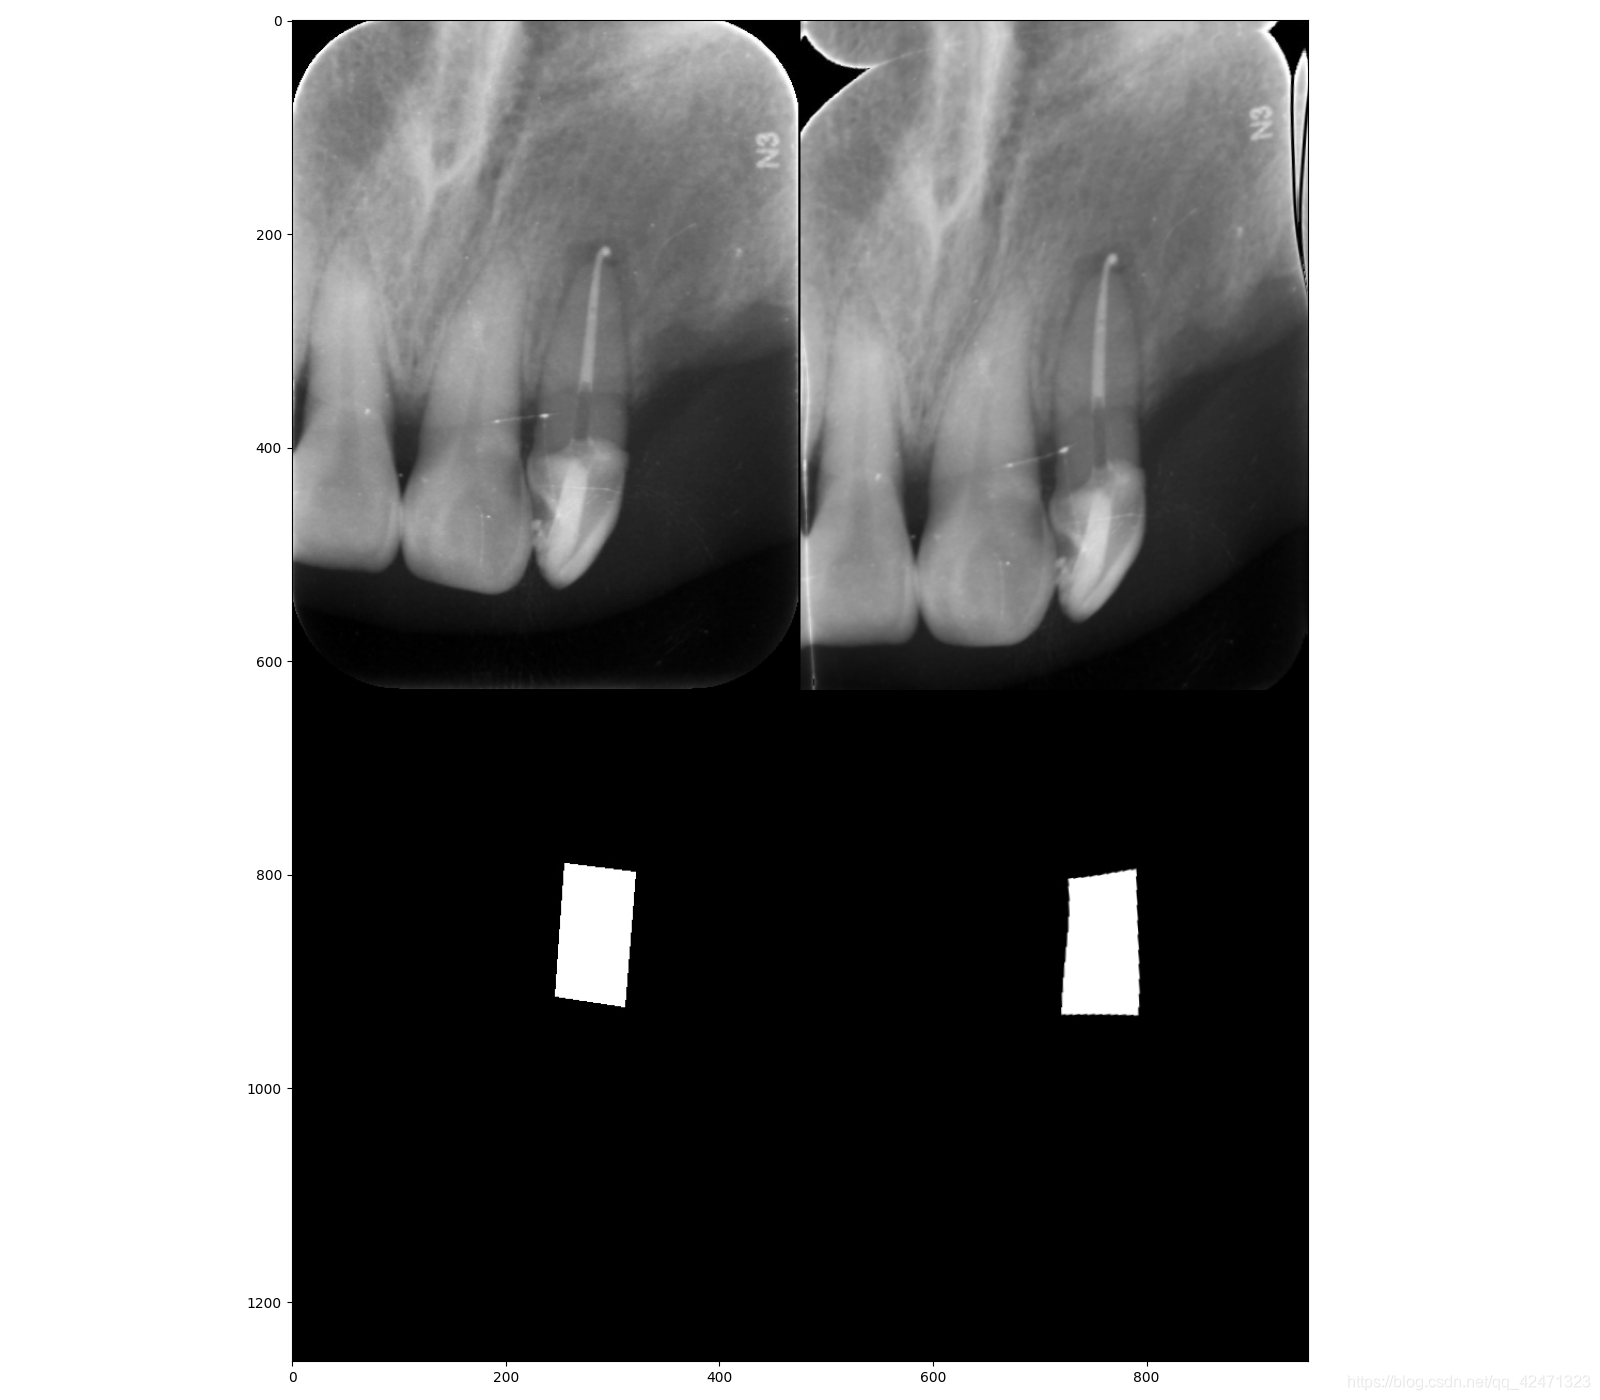

牙片根管治疗需要保存图像细节,适合使用网格形变进行数据扩充

效果图:

本文介绍如何在牙片根管治疗图像中应用网格形变进行数据增强,以保留图像细节,提升处理效果。